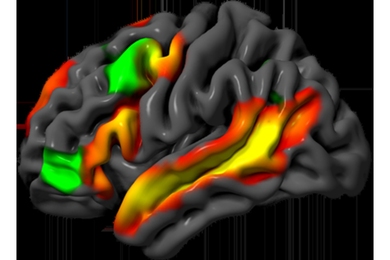

Researchers at MIT are developing a new kind of sensor that detects cancer-related signals inside the bladder and emits a fluorescent light to reveal their presence. By using these nanosensors to map bladder cancer biomarkers in real time, this approach could transform how we monitor and diagnose the disease.